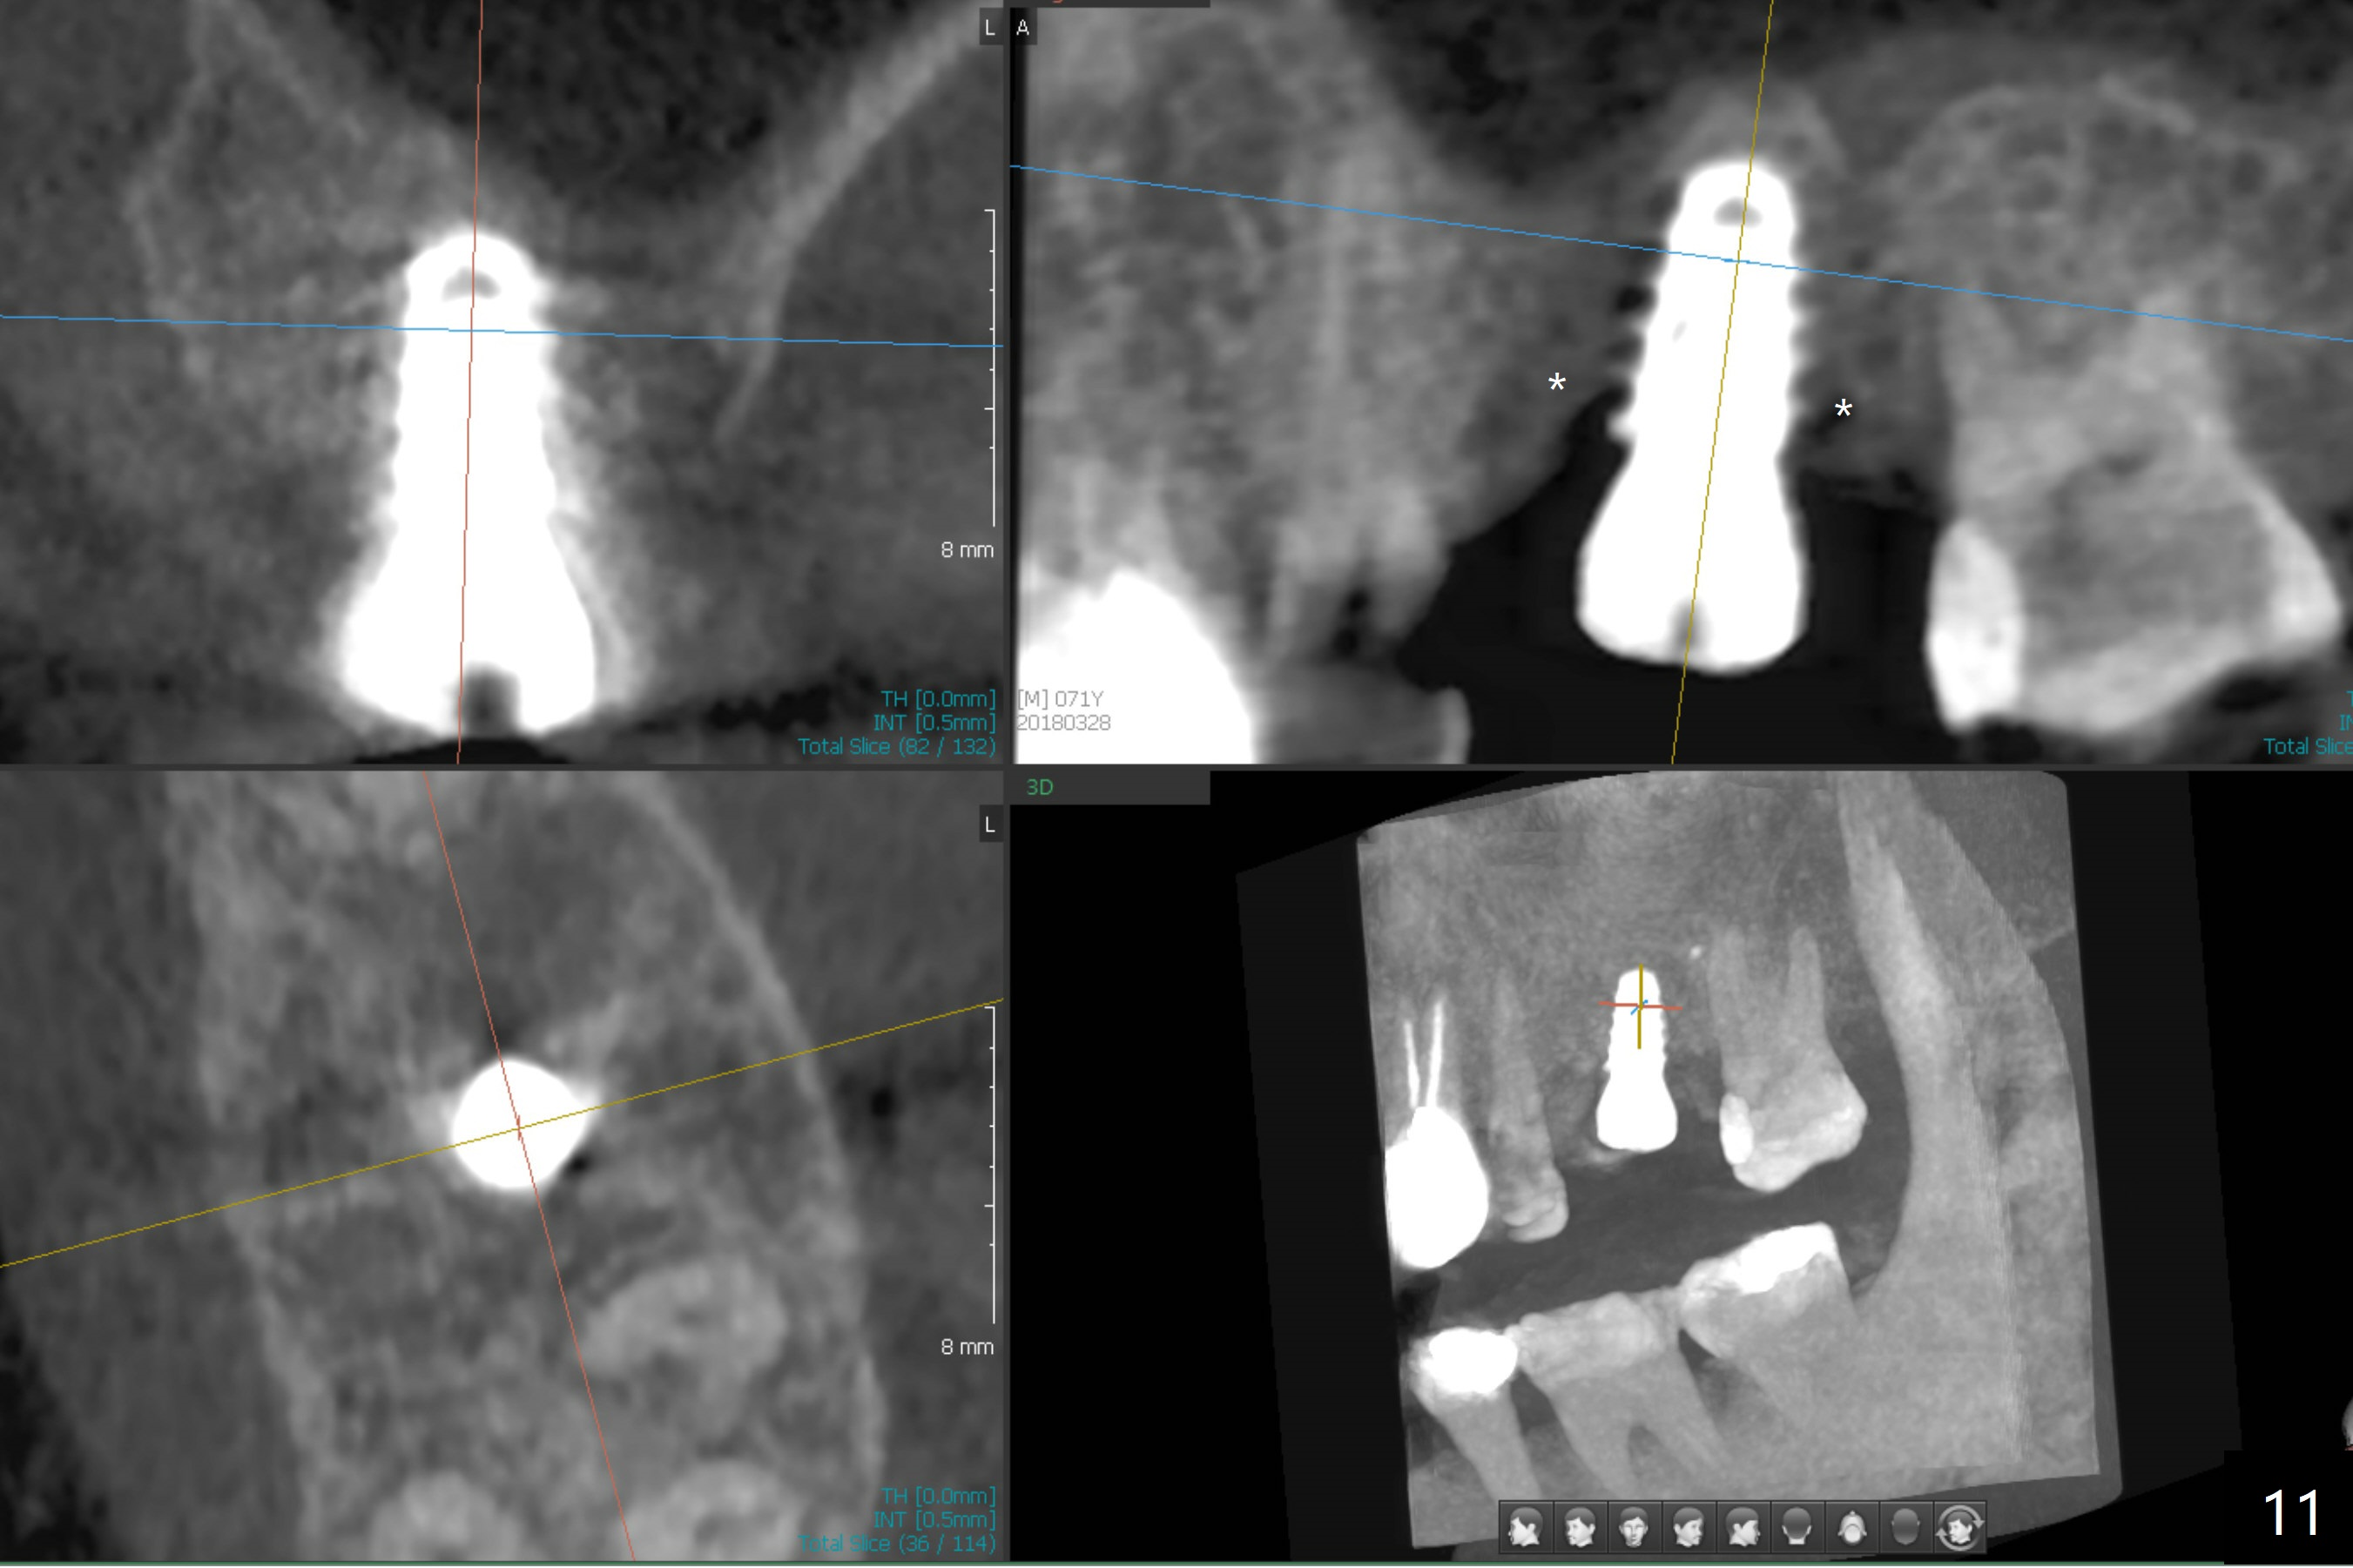

What is unclear preop is the large periapical radiolucency (Fig.1 red dashed line) of the palatal root (P) of the tooth #14.  When the tooth is extracted, it is difficult to remove granulation tissue from the palatal apical socket, which is enlarged (Fig.2 (impression of sockets),3).   The small dimension of the septum (~4x5 mm (Fig.1 pink) is also unrecognized preop, which leads to sinus perforation when 4.8 mm Magic Drill is used.  In spite of use of PRF plug and membrane, allograft does not stay in the osteotomy after placement of 4x11 mm dummy implant or 5 mm tap drill (Fig.4 for 9 mm).  Finally a 5.5x7 mm IBS implant is placed with 30 Ncm (Fig.5).  After placement of Osteogen plug in the apical portion of the sockets, allograft/Osteogen is placed in the remaining sockets (Fig. 5 *).  The latter is partially contained by a 6.5x4(3) mm abutment (A) and ultimately by an immediate provisional.

The implant is mobile 4 months postop (Fig.6).  A 6x2 mm healing abutment is placed next.  Although the implant remains mobile 6 months postop, the bone seems to have become denser around the implant (Fig.7-9).  A healing screw is placed.  When the bone height is limited (<7 mm), place a larger implant (>5.5 mm).  The implant seems to have osteointegrated 8 months postop (Fig.10).  Impression is taken following placing a 6.5x4(3) mm abutment.  The patient reports pain after cementation, which is less when the abutment screw is loose (9.5 months postop, 2 weeks post cementation).  CBCT taken after placement of a healing screw apparently shows loose bone mesial and distal to the implant (Fig.11 *).  The implant trajectory is less favorable.  It seems necessary to change to a large implant with more sold threads (Fig.12).